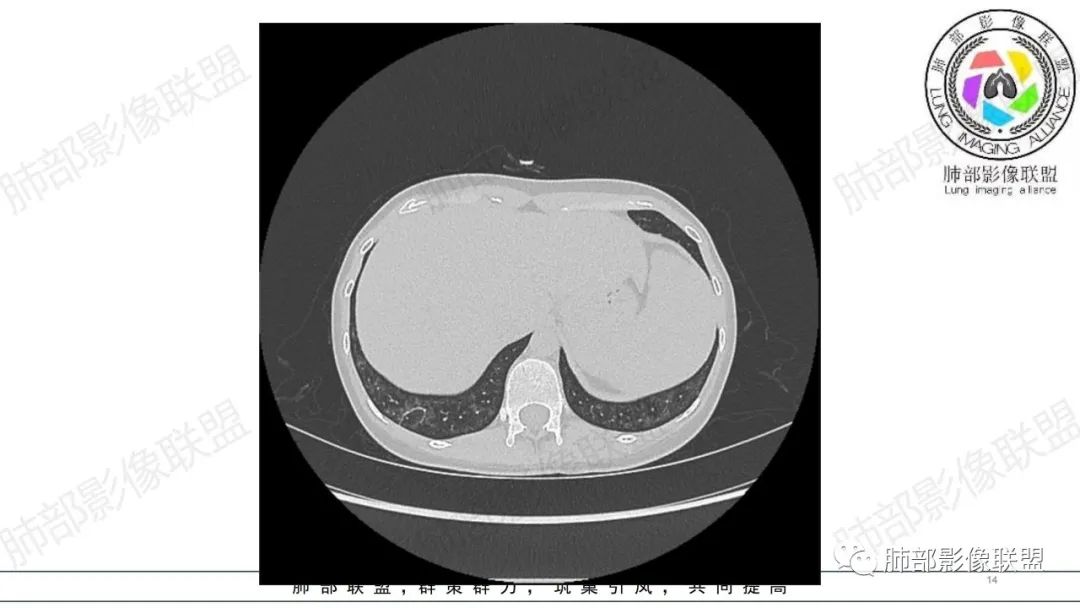

34岁女性患者,“哮喘”病史30年,近期有可疑刺激性气体吸入史;因乏力半年,咳嗽、憋气、发热4天就诊;6.1CT提示双肺广泛毛玻璃影及粟粒样结节,胸膜下闲置及血管周闲置,可见树丫征,部分小叶间隔增厚。考虑:1.过敏性肺泡炎,有可疑刺激气体接触史,胸膜下闲置,广泛毛玻璃影,地图样分布,粟粒结节边界模糊,支持过敏性肺泡炎,但糖皮激素治疗效果不佳,且动态复查血常规血红蛋白进行性降低,过敏性肺泡炎 不符合;2.肺含铁血黄素沉积症:患者30“哮喘”病史,可能为肺含铁症状,肺部CT提示双肺弥漫毛玻璃影及粟粒结节影,中下肺明显,肺底部分小叶间隔增厚,近期咳嗽、憋气、发热,血常规血红蛋白进行性下降,考虑肺含铁急性期症状,但临床无咯血症状,肺含铁不典型。综合考虑:肺含铁血黄素沉积症>过敏性肺泡炎。

肺内气腔磨玻璃结节,肝脾肿大,治疗后间质改变,弥漫大B可能